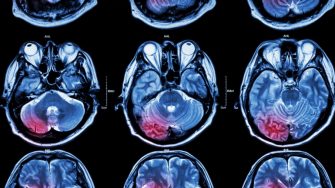

Researchers will be able to access a new Hyperfine low-field MRI – a portable MRI that can move to patients’ bedsides at the point of care, plug into a standard electrical outlet, and acquire critical neuroimages within minutes.

“Together, we’ll develop new models of care, and hospital clinicians can deliver better outcomes for patients by harnessing cutting edge technology like the hyperfine MRI. Even more excitingly, we will amplify our findings and deliver better outcomes for patients irrespective of location through the NSW Telestroke Service.”